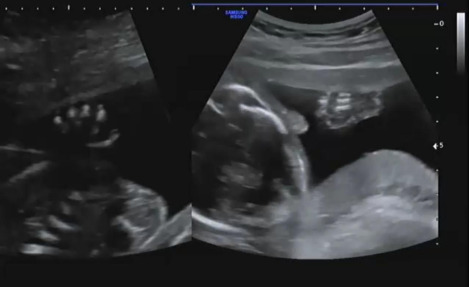

그다음 손가락을 확인하는데 발도 너무나 귀여웠지만 손을 확인할 땐 더욱 귀엽다고 생각했다. 양쪽 손 모두 손가락 5개 있는 것을 확인하는데 햇님이가 주먹을 쥐고 잘 안 보여줬다. 의사가 나의 배를 살며시 흔들어 햇님이의 반응을 보니 그제야 손을 펴 손가락 5개임을 확인시켜줬다.